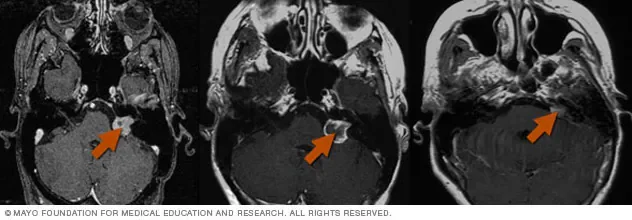

Patient selection relies on strict criteria, including lesion count and volume, yet current clinical guidelines are evolving to manage higher numbers of metastases.

Outcomes are often latent, with benign tumors shrinking over months or years post-exposure.

Multidisciplinary care is the mandated standard for complex brain metastasis, requiring tight coordination between neurosurgeons and radiation oncologists.

Historically, the evolution of brain tumor management has tracked with the miniaturization and accuracy of radiation delivery. Stereotactic radiosurgery has shifted from a novel intervention to a standard pillar of oncology, replacing whole-brain radiation in many contexts to preserve cognitive function and minimize collateral tissue damage. The current discourse within medical journals focuses not on whether SRS works, but on the optimization of fractionation protocols and the integration of salvage treatments for metastatic failure. The 90% deficit suggests that the future of the field is less about finding new physics and more about solving the geometry of healthcare access.